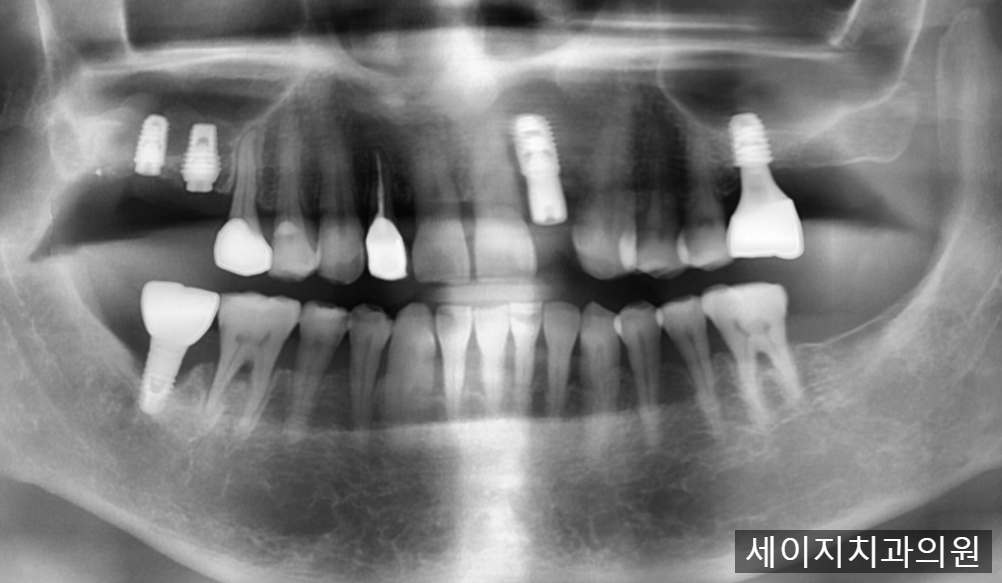

먼저 x-ray와 CT를 이용하여 정확한 뼈의 모습과 치아의 상태를 관찰하였습니다.

CT상으로는 입술에서 가까운 잇몸뼈의 흡수가 관찰되었습니다.

잇몸뼈의 소실이 크기에, 임플란트 진행시 심미적인 요소를 맞추기가 어려워 보였습니다. 때문에 환자분께 브릿지 치료도 하나의 옵션으로 권유드렸으나, 인접한 치아를 갈아내는 것에 대한 부담감이 크다고 이야기 해주셨습니다.

환자분과의 여러번의 상담을 통해서 심미적인 요소를 완성시키기 위해서는 앞니 임플란트 식립과 함께 CTG (Connective tissue graft) 라는 술식이 필요하다는 것을 말씀드렸고 환자분께서도 동의해주셨습니다.